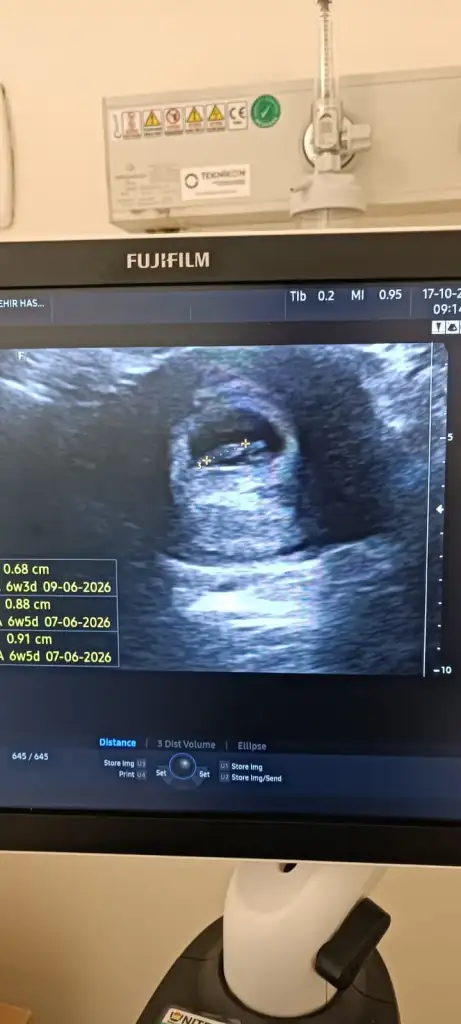

Cinsiyet tahmini

Sizi heveslendirmek istemem hiç oğlum olmadı ama sanki erkek gibi duruyor bacak arasida rabbim gönlünüzdekini hayırlı eyleyip nasıl etsin inşaallah 💜